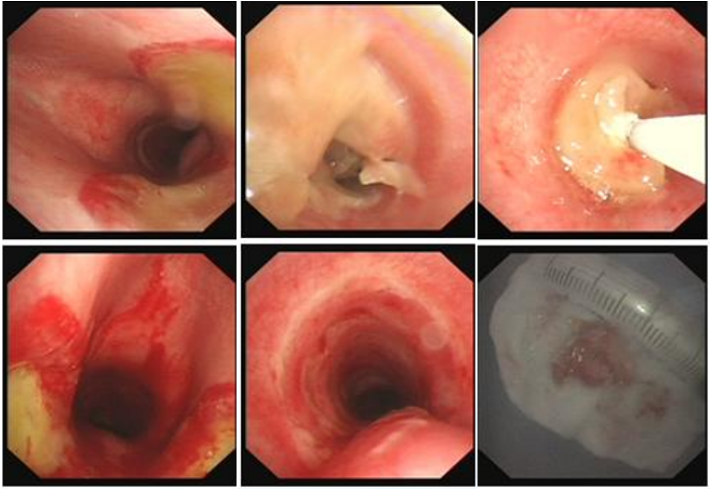

良性中心气道狭窄分为结构性和动力性(6种类型),结构性狭窄包括:管腔内生长(1型),外源性压迫(2型),瘢痕孪缩(3型),扭曲变形(4型);动力性狭窄包括:气道膜部向内膨出(5型),气道软化(6型)。对于动力性狭窄,应考虑用力呼气时的状态,通过操作者的判断,定出最合适、最接近的狭窄程度。治疗方法的制定不仅与气道狭窄程度和长度有关,还与是否存在狭窄过渡段有关。狭窄长度的计算应包括过渡区域。良性气道狭窄形态学分类的诊断方法应通过支气管镜所见及放射学检查来确定。每一个狭窄都可以用4个数字来表示,分别代表部位、类型、狭窄程度、狭窄长度。如:1344代表声门下瘢痕性挛缩性狭窄、狭窄程度>75%、狭窄长度>5 cm,这是一种非常难以处理的良性气道狭窄;2311代表气管瘢痕性蹼状网眼狭窄、狭窄程度<25%、狭窄长度<1 cm,这是一种比较容易处理的良性气道狭窄。热消融技术(APC、电凝、激光)是治疗增生性气道腔内病变(如良性肿瘤和单纯肉芽)的简单、快速的方法。但在治疗瘢痕狭窄病变时,其本身可对气道造成更重、更大范围的损伤,引起更为严重的肉芽组织增生和瘢痕形成,从而导致复发率高,且治疗次数的增加可导致狭窄病变范围增大并最终破坏软骨,导致气道塌陷,使患者彻底失去治愈的机会。电凝和APC仅适合管腔内生长的1型良性中心气道狭窄,并不适合其他类型良性中心气道狭窄的治疗。即便如此,基底部的处理也应避免使用此类治疗方法。针形电刀与气道黏膜接触面极小,不会造成损伤面扩大,瘢痕性气道狭窄的治疗宜选用针形电刀进行切割、松解。因激光也有切割的作用,因此也可选用激光治疗,钬激光、铥激光控制烧灼深度最浅可达0.4 mm,因此更适合良性瘢痕增生性气道狭窄的治疗。冷冻治疗分为冷冻切除(简称冻切,cryoextraction)及冷冻消融(简称冻融,cryoablation)。对于腔内生长的病变可采用冻切治疗,由于容易出血,其安全性不如热消融技术。对于瘢痕病变,冻切技术无法实施,则采用冻融治疗,冻融治疗不促进肉芽组织增生。与热消融相比,冷冻不易导致软骨损伤。通常在热消融治疗接近气道壁时或球囊扩张后采用冻融治疗处理剩余病变,有利于减轻瘢痕再狭窄发生的速度与程度。严重气道狭窄在开通气道前不要使用冻融,因其可引起气道水肿,加重气道狭窄,从而导致窒息。因此,冻融治疗后肺部体征监测及气管镜复查十分重要。机械扩张技术包括球囊扩张和硬质支气管镜扩张,并发症有气道撕裂、再狭窄、出血。(1)球囊扩张:是治疗瘢痕性气道狭窄最主要的技术,其优势是患者治疗后无明显的狭窄段延长,狭窄复发时再狭窄的程度比热消融治疗后轻得多,有利于维持气道复张的疗效。对气管黏膜损伤小,可以在软镜下应用,但需要中断通气。对于挛缩、韧性较强的瘢痕,可先用针形电刀进行切割以松解瘢痕;避免直接暴力球囊扩张,导致气道膜部的撕裂伤。(2)硬质支气管镜扩张:其优势是扩张时不需要中断通气,安全性更好。针对瘢痕肉芽组织增生导致介入治疗后的气道再狭窄,可采用气道狭窄部位局部应用药物的方法抑制瘢痕肉芽组织增生。介入治疗后气道再狭窄可选择的治疗药物有:糖皮质激素、丝裂霉素C、曲尼斯特、紫杉醇等。通过直接植入放射性物质(最常用铱-192)或经过可弯曲支气管镜近距离照射气道瘢痕肉芽组织,促使成纤维细胞凋亡。气道支架置入首选硅酮支架,禁用金属裸支架。支架治疗应作为良性气道狭窄最后选择的治疗技术,启动气道支架治疗的指征:①应用前述各种治疗方法疗效不佳,不能维持气道通畅;②在确定外科手术前临时放置;③外压性气道狭窄;④气道软化、塌陷且无法或不准备行外科手术治疗。病例1:17岁,女性,骨折术后肺炎插管,拔管后(2月14日)气道明显狭窄(图3)。2月15日评估:HR 113次/min,R 24次/min,静息下SpO2 97%(FiO2 50%),咳嗽及说话后喘鸣,有阵发性血氧下降。会诊后拟行急诊介入治疗。2月15日无痛气管镜示:声门下腔黄色及乳白色膜状坏死物,气管上段大量黄色坏死物并管腔重度阻塞,仅见小孔,以冷冻法清除坏死物后管腔通畅(图4)。术后气促明显改善,无需吸氧。病例2:77岁,女性,呼吸困难2个月,加重3天,于2023年12月2日入院(2023年9月气管插管,插管后20余天后拔管)。入院当天查体:HR 125次/min,R 30次/min,静息下SpO2 96%(高流量FiO2 30%),PaCO2 56 mmHg。患者术前影像如图5所示。12月3日查体:HR 140次/min,R 35次/min,BP 190/90 mmHg,SpO2 68%~75%(FiO2 100%),躁动不安,急查血气分析:PaCO2 89 mmHg。紧急床旁无创通气支持下气管镜:气管上段狭窄80%以上,较多黄白黏稠分泌物在狭窄口随呼吸摆动,予抽吸后SpO2升至98%,见狭窄处直径约3 mm,外径5.2 mm,软镜无法进入,遂置入导丝,10#球囊扩张多次,狭窄部位增宽,外径4 mm气管镜引导6.0号气管导管经口插管成功(图6)。插管后患者HR 98次/min,复查血气分析示PaCO2 41 mmHg,氧合指数300 mmHg以上。12月4日气管镜示:右鼻旁路进镜,缓慢退气管导管至声门,距声门3 cm处狭窄,直径7 mm,予12#球囊扩张1 min,2次,未见出血,扩张后直径约12 mm,地塞米松局部保留,气管导管复位(图7)。12月5日拔除气管导管。12月6日气管镜示:气管上段瘢痕狭窄(管径10~12 mm),少许膜状坏死、未见肉芽,予以清除坏死物,7点、11点冻融,术毕注入地塞米松5 mg(图8)。12月13日气管镜示:气管上段瘢痕狭窄(管径12 mm左右),少许膜状坏死、未见肉芽,予以清除坏死物,7点、11点冻融,术毕注入地塞米松5 mg(图9)。